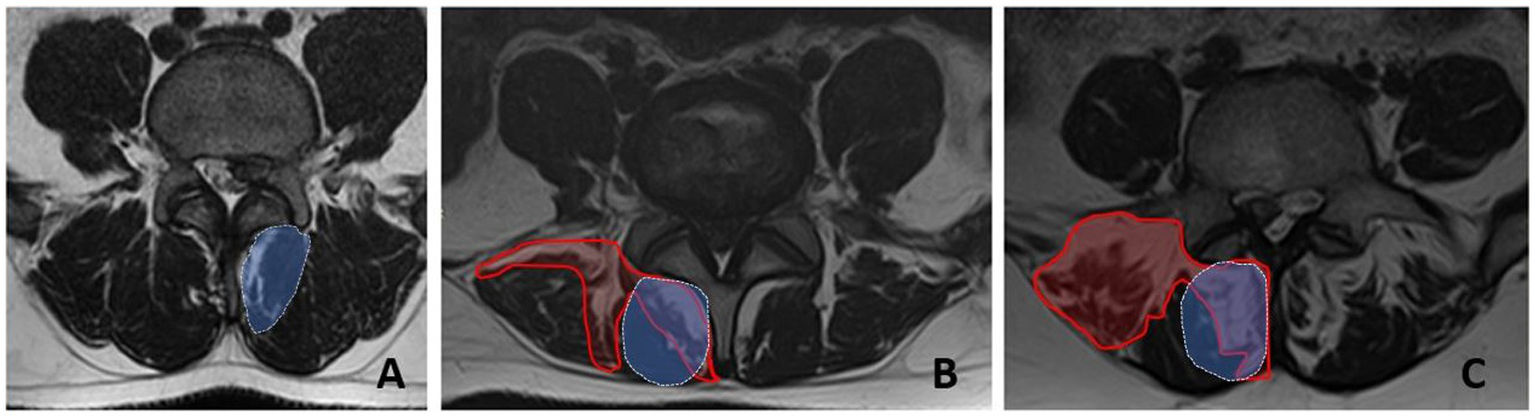

Visual assessment of the PM structure was based on axial T2-weighted MRI sections at the level of the herniated L4-L5 disc. The severity of PM fatty infiltration was used to divide the patients into 3 groups: “Grade 0” - 0-10%, “Grade 1” - 10-50%, and “Grade 2” - more than 50%. In general, the degree of fatty infiltration of PM was previously reported to be correlated with that in isolated m. multifidus (Figure 2) (9).

Figure 2

Fatty infiltration grades for the paraspinal muscles at the L5 level measured by MRI (axial sections). A - grade 0, B - grade 1, C - grade 2. The area of fatty infiltration is circled in red. The area of m.multifidus is circled in blue.